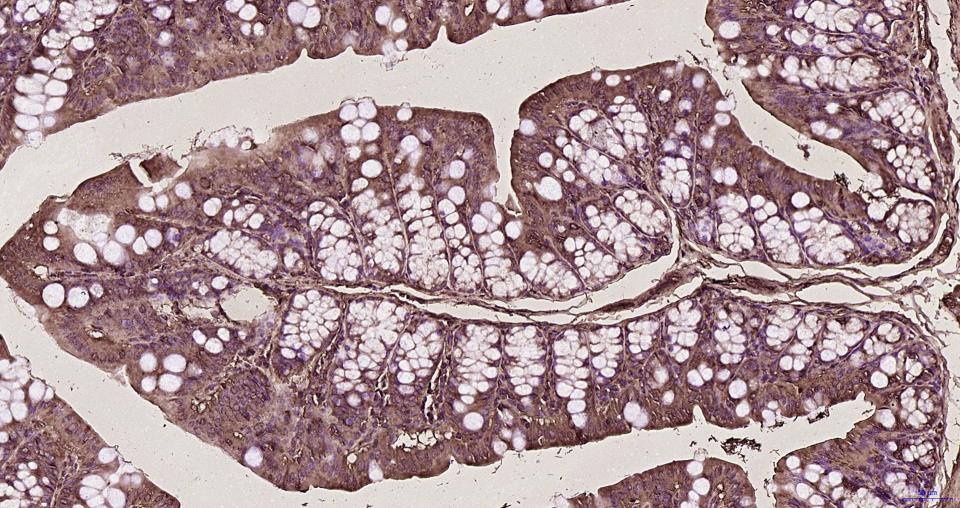

Paraformaldehyde-fixed, paraffin embedded Human stomach; Antigen retrieval by boiling in sodium citrate buffer (pH6.0) for 15 min; Antibody incubation with RhoA/B/C Monoclonal Antibody, Unconjugated (bsm-61200R) at 1:200 overnight at 4°C, followed by conjugation to the bs-0295G-HRP and DAB (C-0010) staining.

Paraformaldehyde-fixed, paraffin embedded Mouse stomach; Antigen retrieval by boiling in sodium citrate buffer (pH6.0) for 15 min; Antibody incubation with RhoA/B/C Monoclonal Antibody, Unconjugated (bsm-61200R) at 1:200 overnight at 4°C, followed by conjugation to the bs-0295G-HRP and DAB (C-0010) staining.

Paraformaldehyde-fixed, paraffin embedded Rat stomach; Antigen retrieval by boiling in sodium citrate buffer (pH6.0) for 15 min; Antibody incubation with RhoA/B/C Monoclonal Antibody, Unconjugated (bsm-61200R) at 1:200 overnight at 4°C, followed by conjugation to the bs-0295G-HRP and DAB (C-0010) staining.